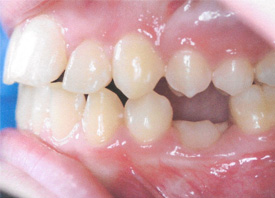

Causes of ankylosis Ankylosis is a condition in which a tooth fuses to the bone, preventing normal tooth growth. This condition can happen to a primary or permanent tooth and can be caused by trauma o....